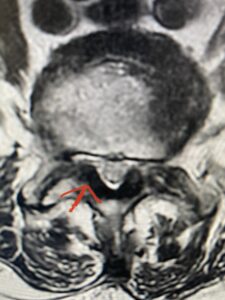

Fig 2 Axial T2-weighted lumbar MRI demonstrating severe lumbar stenosis at L4-5 secondary to thickened ligamentum flavum “knobs” (red arrow) contributing to central and lateral recess stenosis.

Another patient is a 62 year-old female with progressive low back pain and right leg pain and numbness that radiates to the top of her foot. She tried physical therapy and epidural injections. MRI demonstrated severe L3-4 stenosis and a grade 1 spondylolisthesis (Fig 4). There was L5-S1 and L4-5 disc collapse with modic end-plate changes. Biomechanically because of the significant degeneration of these disc spaces which stiffened the L4-S1 segment more stress was placed on the L3-4 segment, resulting in significant premature degeneration and compensatory stenosis and segmental instability. The MRI also showed pathologically, because of the slip, the L3 inferior processes were more anteriorly oriented and hence contributing to the majority of the lumbar canal compromise. Note the more sagittally-oriented facets in this case compared to the prior case (Fig 5). The patient underwent a decompressive laminectomy with attention of removing the inferior processes of L3 to fully decompress the canal. We also performed an L3-4 fusion with instrumentation (Fig 6). The patient had an uneventful postoperative course with improvement of leg pain. Of note with relief of the disabling leg pain patients are generally very happy. Patients can often manage their low back pain; it is the leg pain that they just can’t tolerate.

Fig 5 Axial T2-weighted lumbar MRI demonstrating significant L3 inferior facet contribution of severe stenosis (blue arrow)